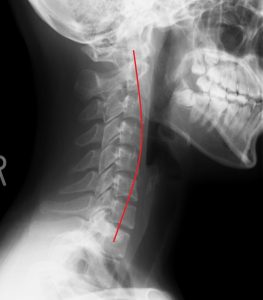

写真はストレートネックのレントゲン画像です。

赤いラインが正常な骨のカーブ。